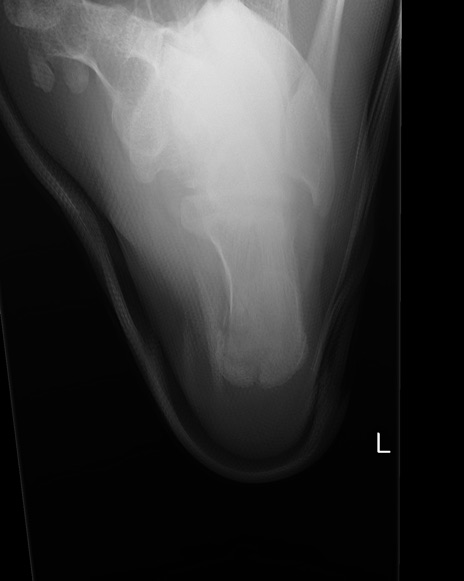

症例37 踵骨レントゲン(左正面像)

【症例】50歳代男性

【主訴】左踵部の痛み、腫脹

【現病歴】4日前に1.5m程度の高さのトラックの荷台から荷物と一緒に転落し、左足部を打撲。近医受診し、当院へ紹介受診となる。

【身体所見】左踵部の腫脹、圧痛あり。

異常所見と診断は?